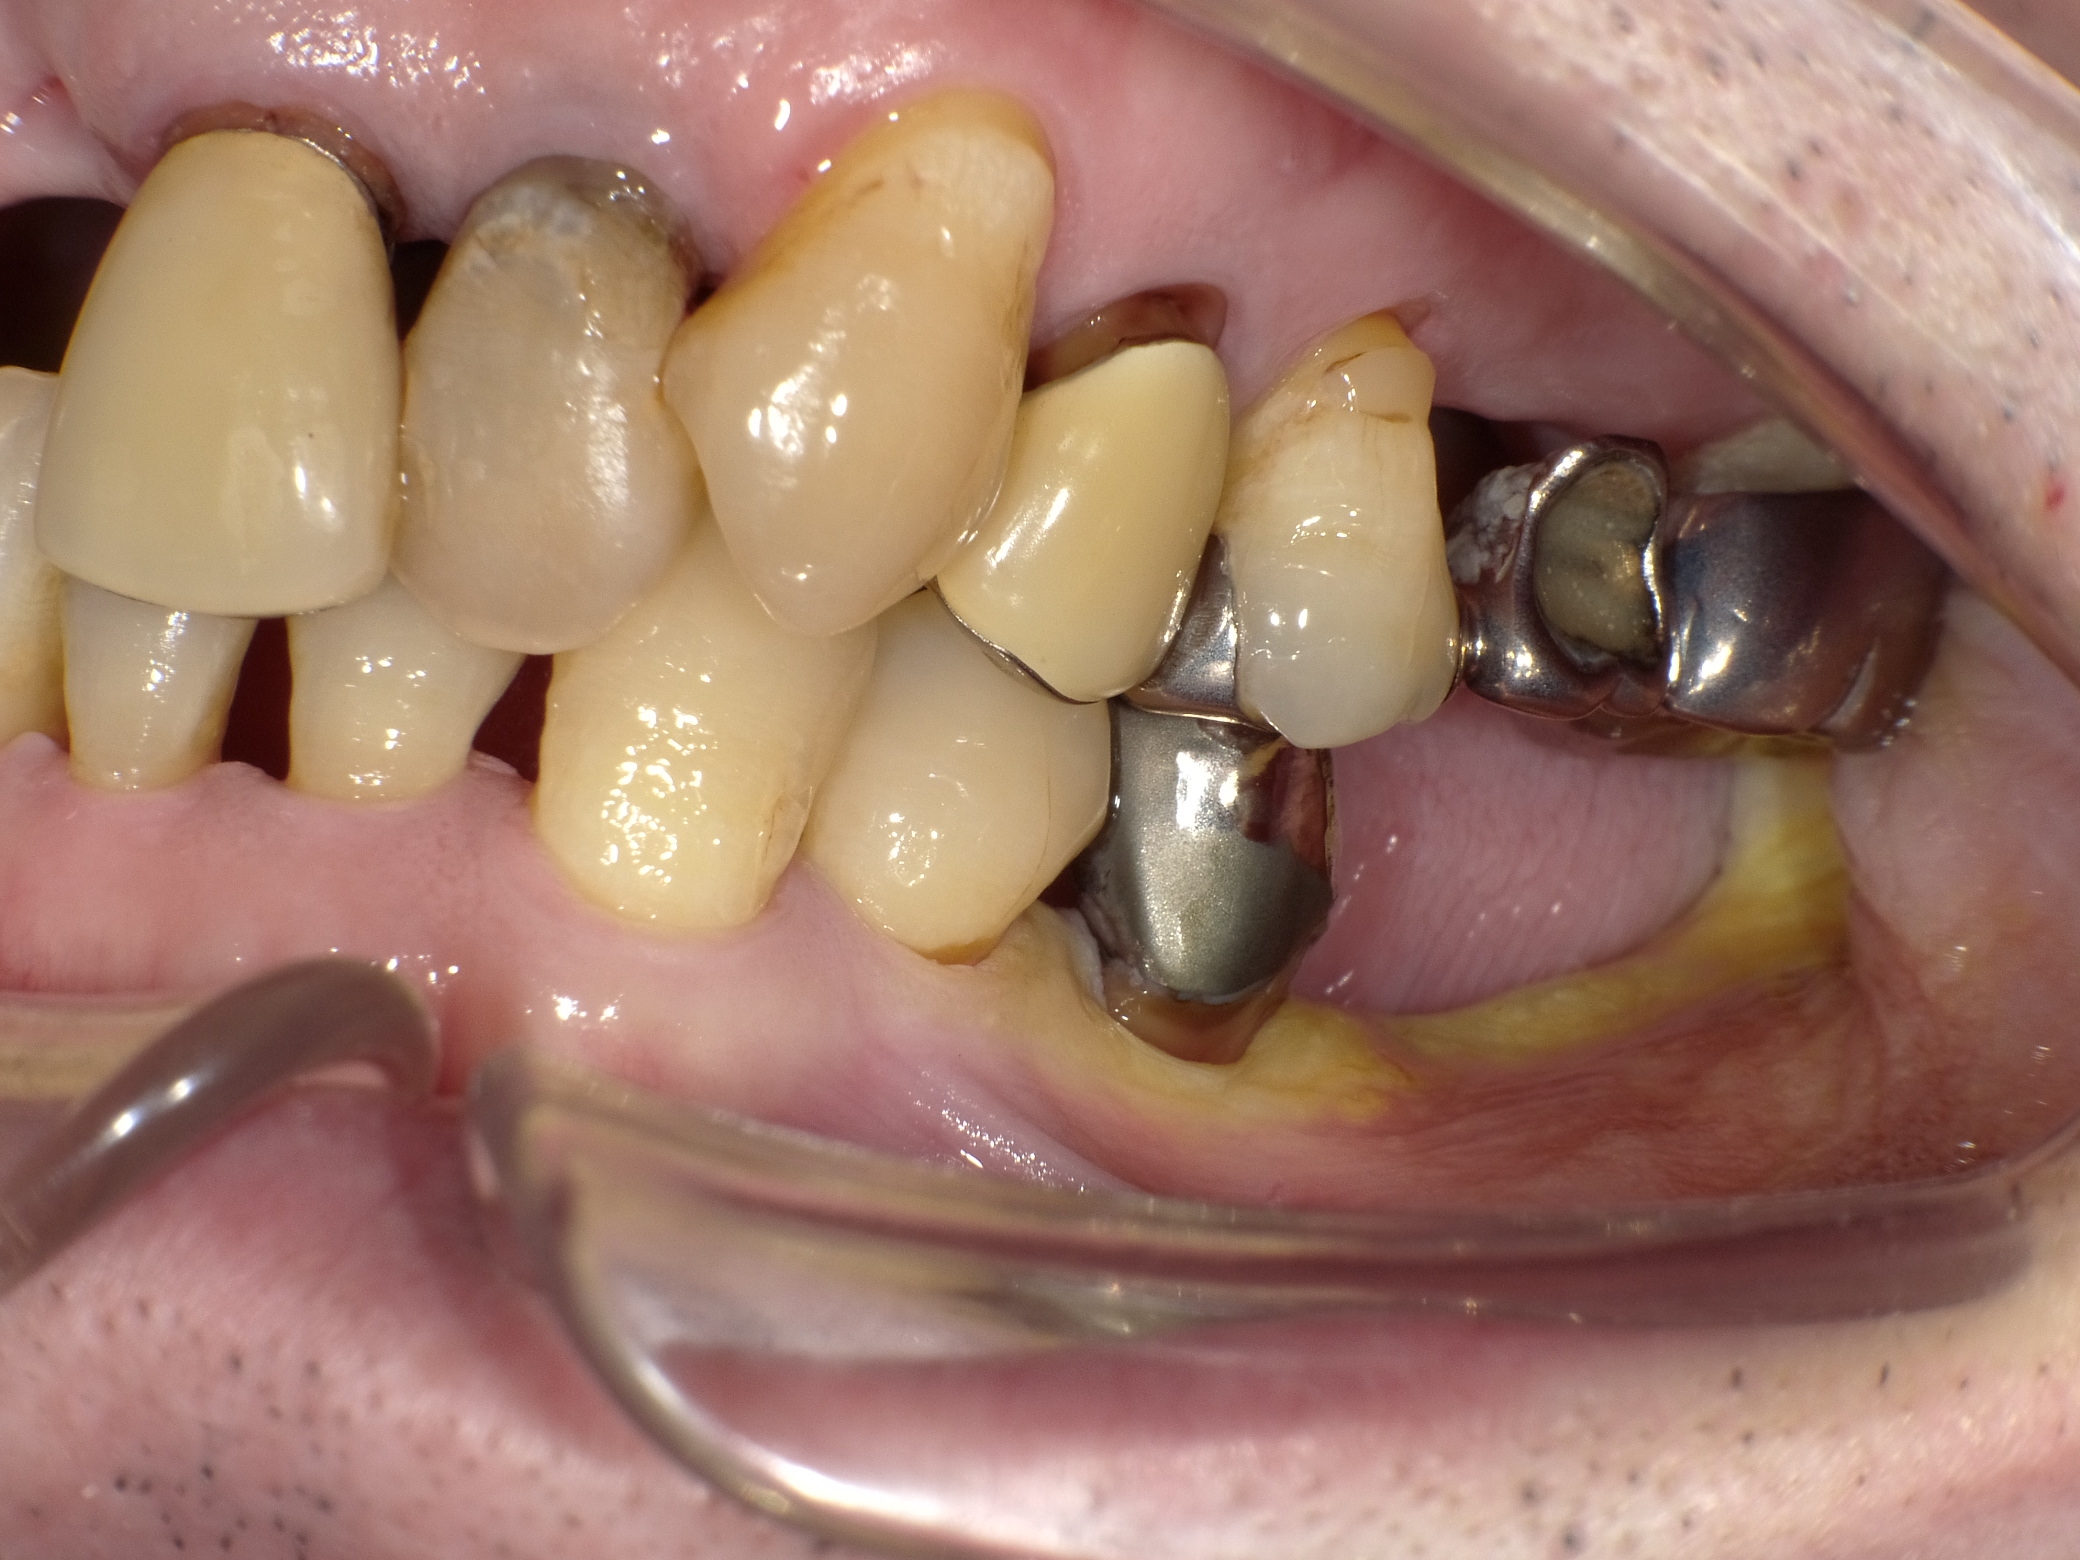

左下2本インプラント症例

主訴 奥歯でしっかり咬めるようにしたい(男性) 治療内容 左下の奥歯2本をインプラントにて治療しています。プラマRFインプラントを埋入。

手術後3ヶ月待ち、骨とインプラントが固まったことを確認し、二次手術後に型取りを行っています。当院では、ほとんどの症例でデジタルでの型取りを行っています。

インプラントを埋入した部位に型取り用のパーツをはめ、3Dスキャナーにて型取りをし、ジルコニアクラウンの被せ物を作製しています。完成後の咬合面は状態を確認後、埋めていきます。

治療期間 約4ヶ月

費用 総額 ¥700,000-(税別) リスクと副作用 ・外科治療となるので、お身体の状態によっては受けれない場合がある(広範囲に適用可能な治療ですが、個々の患者様の状況によって適用外な場合もある)

・術後に多少の痛みや腫れが出ることがある -